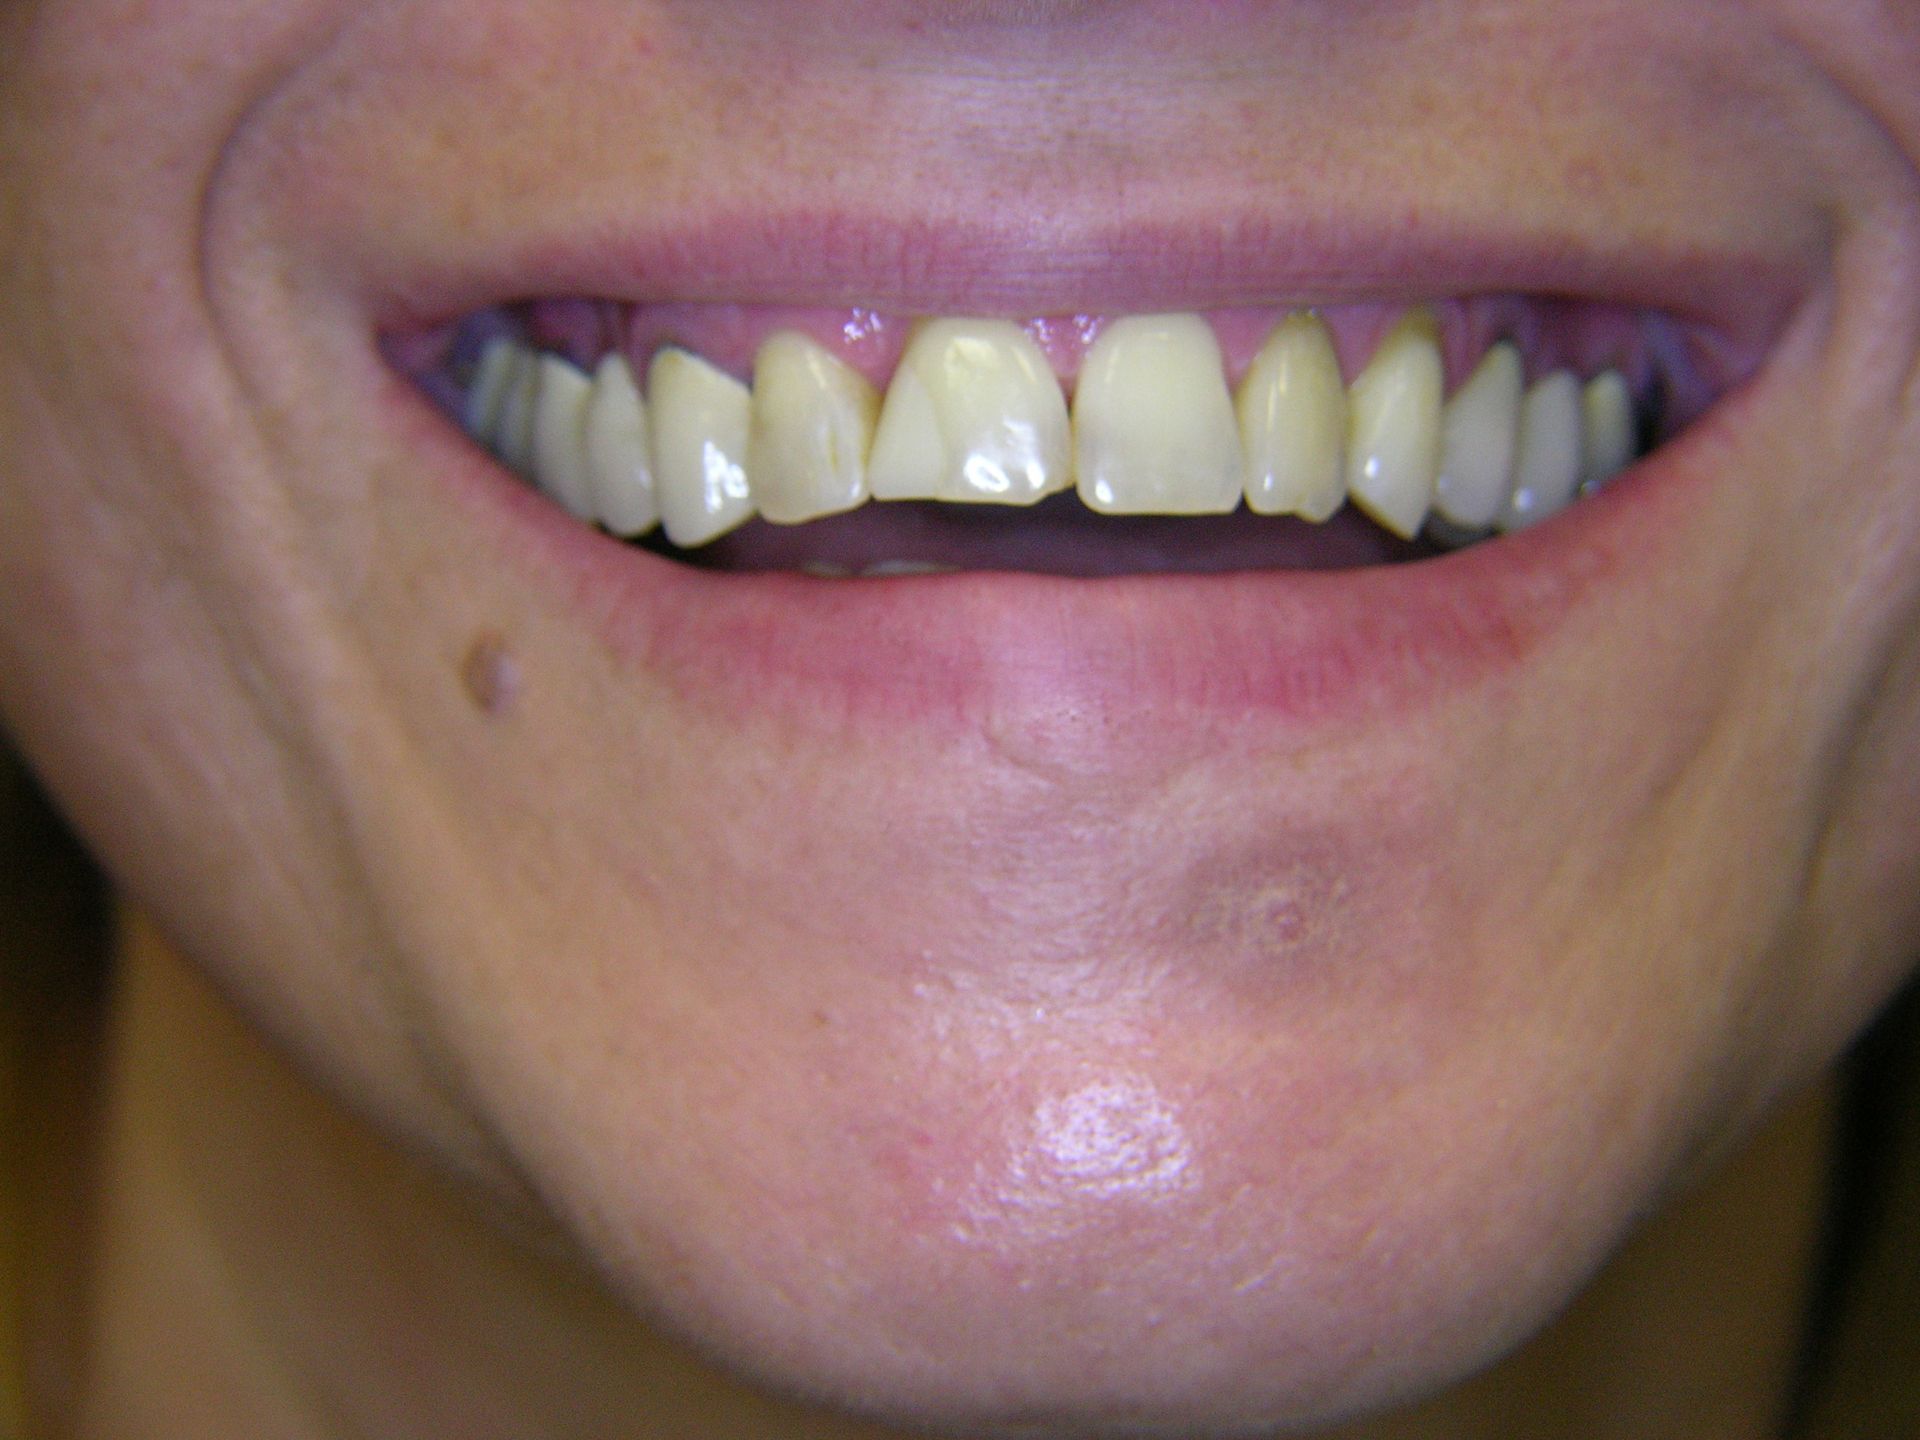

Beispiele von Versorgungen